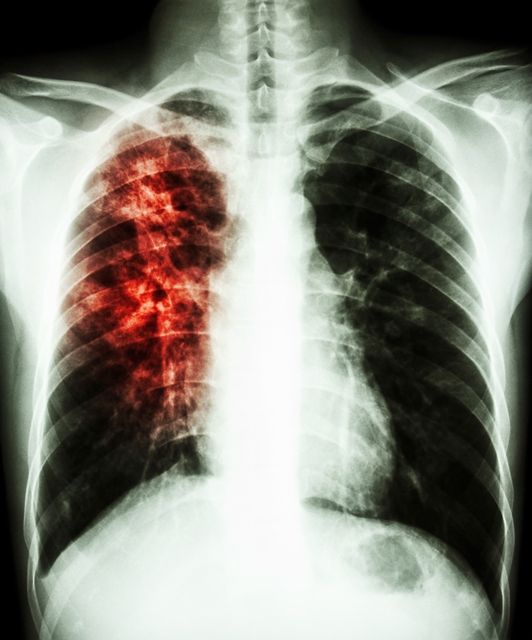

Αναπνευστικές Παθήσεις

1. Χρόνια Αποφρακτική Πνευμονοπάθεια (ΧΑΠ)

3. Λοιμώξεις Αναπνευστικού

4. Ιδιοπαθής Πνευμονική ίνωση και διάμεσες πνευμονοπάθειες

11. Επαγγελματικές παθήσεις των πνευμόνων

12. Αγγειακές παθήσεις των πνευμόνων και Πνευμονική Υπέρταση